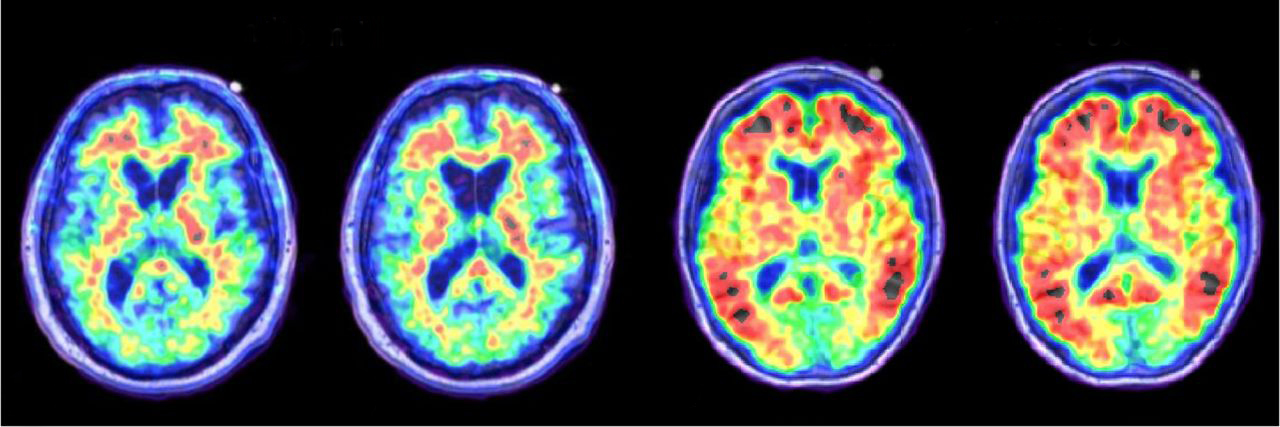

PET-Bilder ermöglichen es, biologische Prozesse wie Blutfluss, Stoffwechsel oder Proteinkonzentrationen im Körper zu visualisieren. Hierzu wird dem Probanden ein Radiotracer injiziert, wodurch Moleküle mit radioaktiven Isotopen durch die Blutbahnen verteilt werden. Die Konfiguration des Moleküls bestimmt die zu überwachenden biologischen Prozesse.

Christophers Master-Thesis behandelt das menschliche Gehirn bei der Alzheimer-Erkrankung. Alzheimer veränderten den Abbau des Amyloid-Vorläuferproteins wodurch der sogenannte Amyloid-Plaque entsteht. In seiner Master-Thesis geht Christopher der Frage nach, wie sichergestellt werden kann, dass unterschiedliche PET-Scanner mit unterschiedlichen Auflösungen die Menge an Amyloid-Plaque einheitlich bestimmen können. Hierzu muss die Auflösung jedes einzelnen PET-Scanners bestimmt werden und auf eine bestimmte Auflösung reduziert werden. Das führt dazu, dass die Alzheimer-Krankheit in einem frühen Stadium erkannt werden kann.